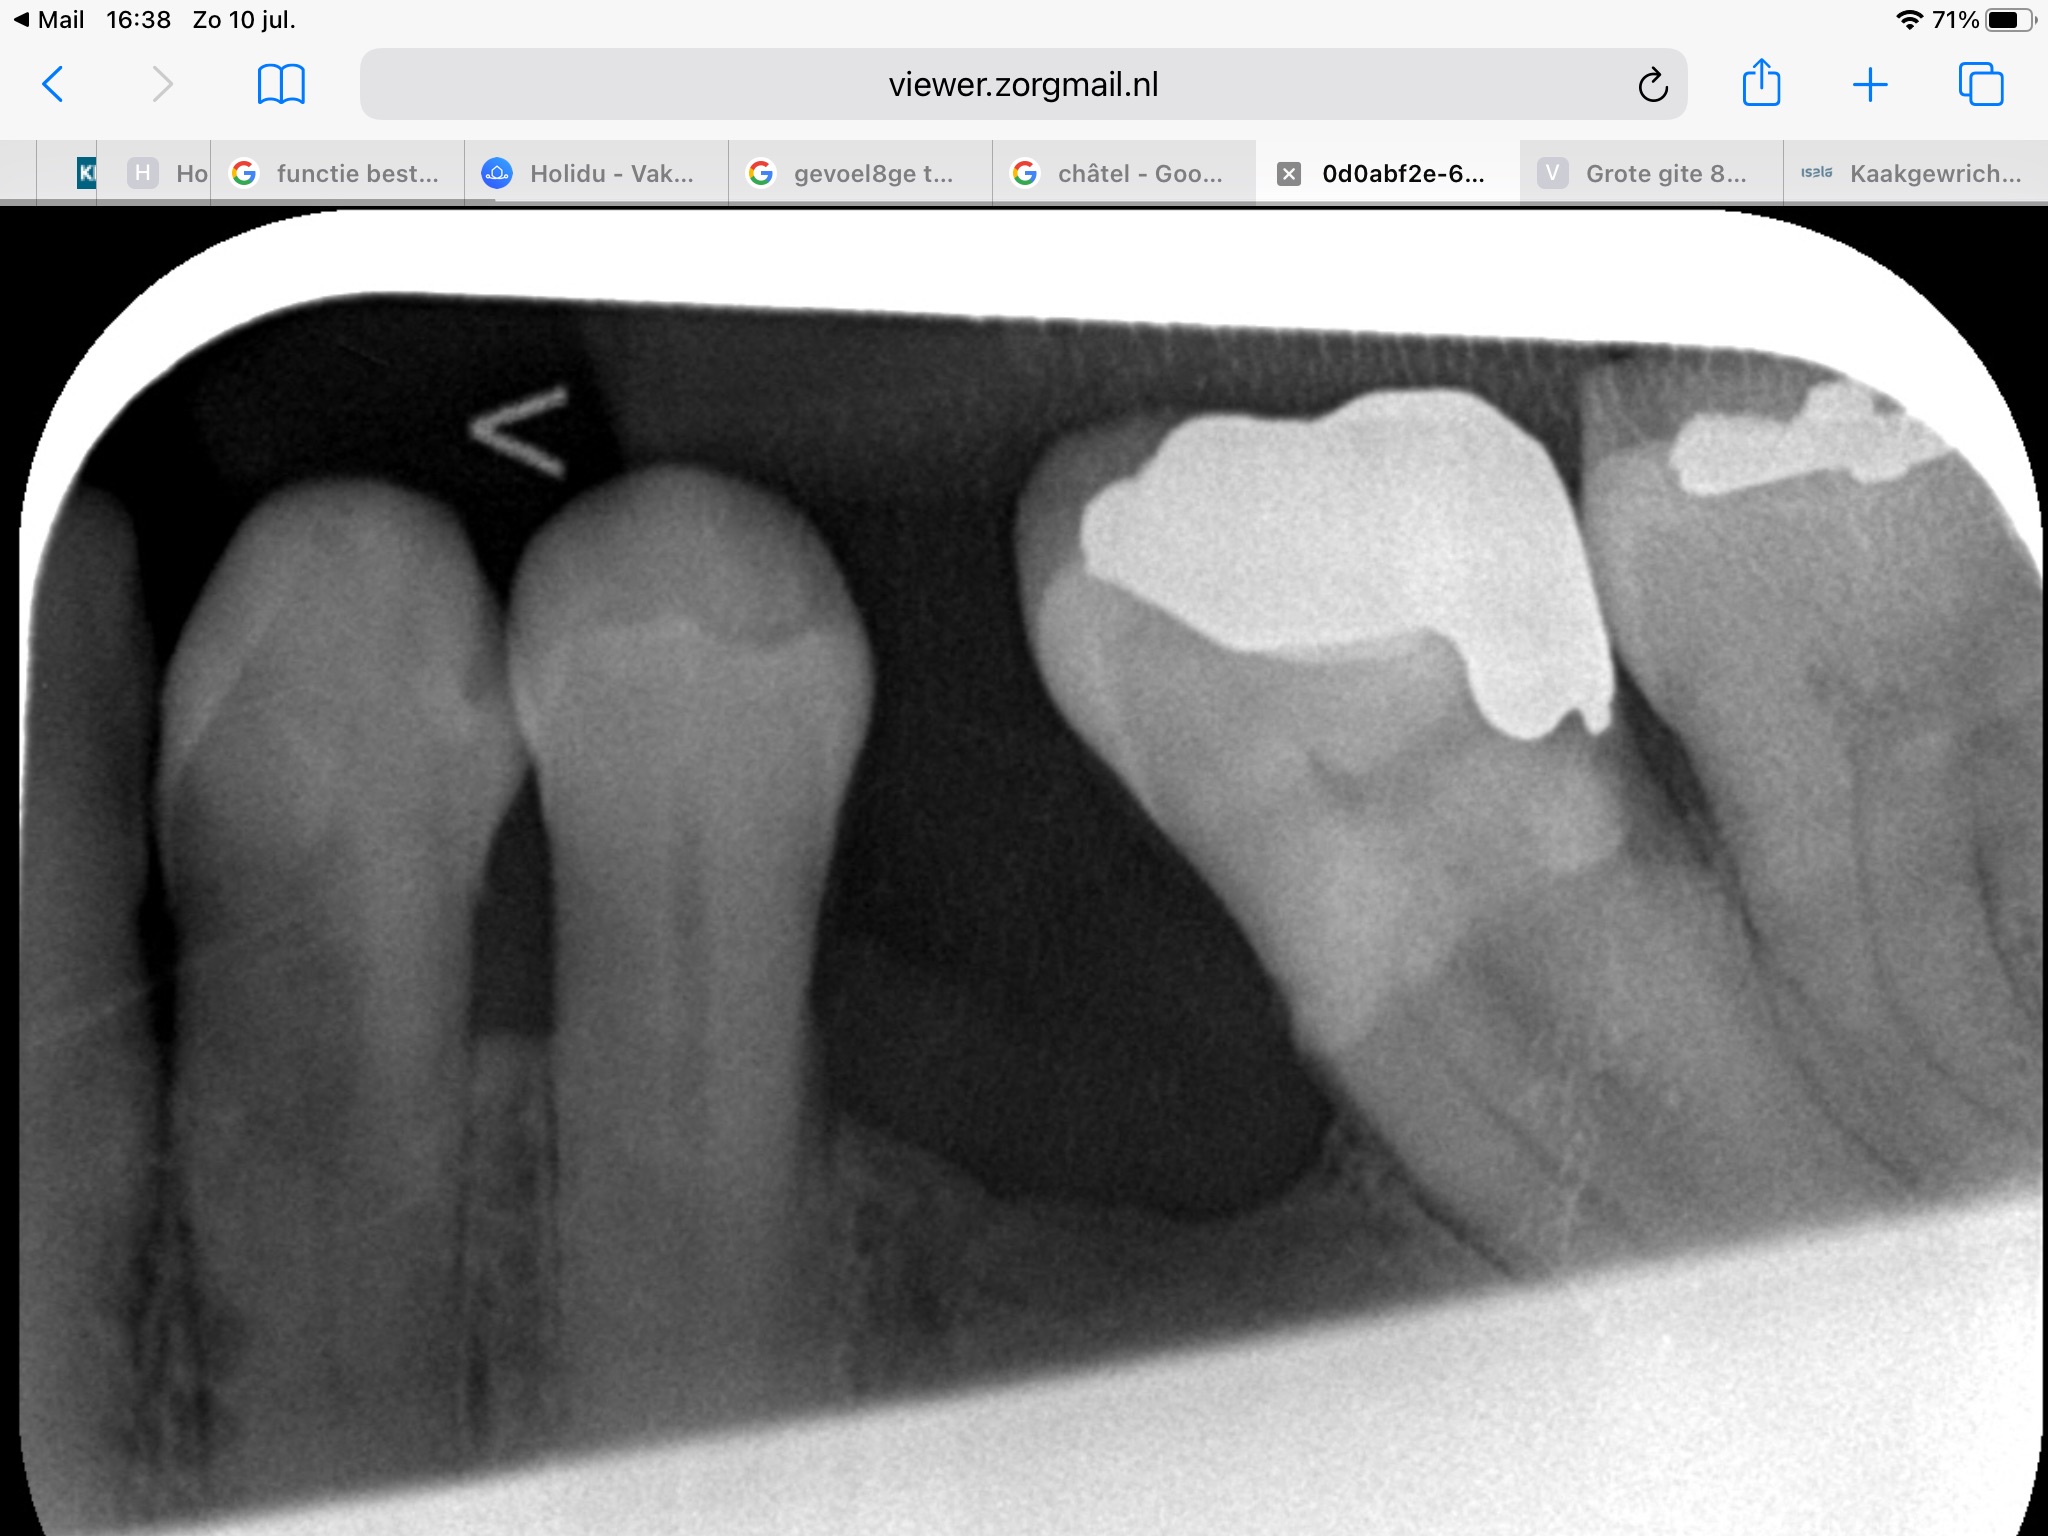

37 blijkt uit het foto secunder cariës

endo start lukte niet, kanalen zijn dichtgeslibd advies extractie tot dan ab kuur.

Wat in de reguliere praktijk niet lukt, lukt soms wel bij de ervaren endodontoloog. Jammer dat voor de getrokken kies niet een vervanging is gemaakt. Duidelijk te zien dat de 37 daardoor naar voren is gekanteld. Afhankelijk vd situatie v uw gebit aan de andere kant en boven zijn er vele opties. Afhankelijk v wat u financieel kan/wil. Dus bij behoud overleg/behandeling met een endodontoloog. Vraag is: moet de kies behouden blijven en wat zijn de opties als getrokken wordt. Dit afhankelijk v d behandel planning voor uw gebit in de komende jaren. Een duidelijk behandel strategie met uw tandarts bespreken.